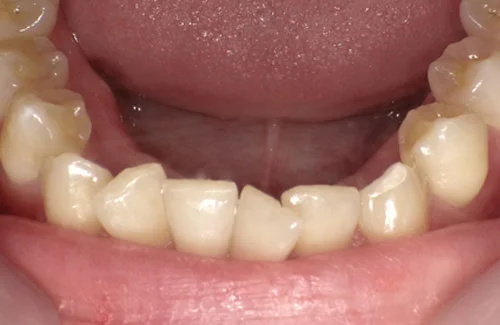

<症例7>歯がガタガタで噛み合わせが悪くお悩み

抜歯無し・マウスピースのみで矯正した症例です。

もともと歯列弓が非常に狭く、V字に近い形をしていたので噛み合わせも非常に不安定でした。

また、下顎前歯部がかなり上の方に生えていたため、下の前歯が上の前歯を突き上げてしまい出っ歯の状態になっていました。

現在では見た目はもちろん、臼歯の噛み合わせも改善しております。

奥歯の患者様も大喜びでした。

患者様と症状

主訴:歯のガタガタ、噛み合わせが悪い

性別・年齢:20代女性

問題点:叢生(重度)、V字歯列弓、ディープバイト

診断:前歯部の叢生を伴うアングルⅠ級、骨格性Ⅰ級の不正咬合

主なリスク:臼歯の移動に伴い一時的に咬合しにくくなる、歯肉退縮

症状:叢生(そうせい) 過蓋咬合(かがいこうごう)

治療内容

治療期間:1年10ヶ月

治療費用:990,000円(税込)

プラン:Full2プラン

抜歯:無し

再診治療費:無し

追加治療費:無し

保定装置費:無し

治療前後の写真